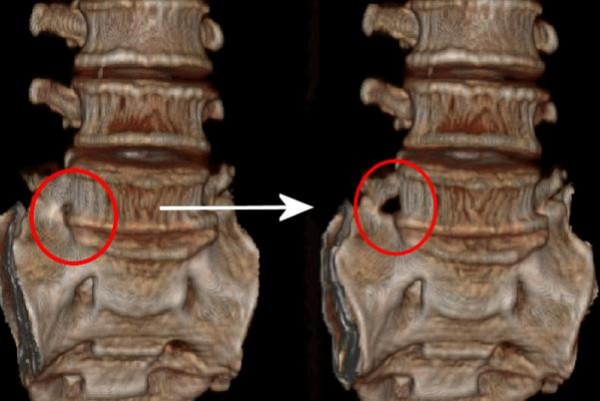

김순임씨는 좋은아침병원 척추센터에서 극외측 협착증으로 확진을 받고 미세도관 감압술로 수술을 받았다. 미세도관 감압술은 직경 18 mm의 가는 관을 수술부위에 삽입하고 그 도관을 통하여 미세감압수술을 현미경을 보면서 하는 수술로 전신마취나 수혈이 필요 없는 최소침습수술이다. 김순임씨는 수술 당일 통증이 사라져 정상적인 보행이 가능해져 매우 만족하였고 수술 다음날 퇴원하여 현재 정상적인 생활을 하고 있다. (동그라미 친 부분이 좁아져 있던 부위를 미세도관 감압술로 넓힌 부위이다)